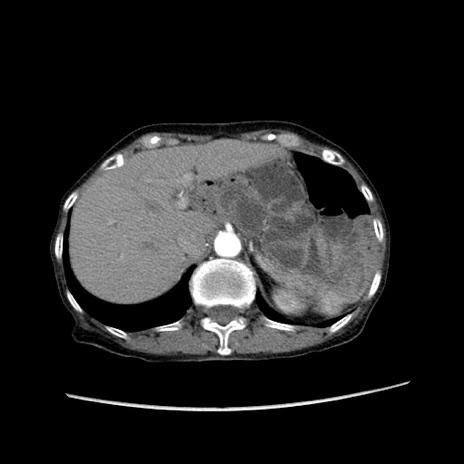

冠状断像

【症例】80歳代女性

【主訴】胸のつかえ感

【現病歴】約9時間前に食後から胸のつかえた感じあり、嘔吐あり、来院。

【既往歴】胃癌(全摘)、胆摘、虫垂炎

【身体所見】心窩部に圧痛あり、反跳痛なし。

【データ】WBC 5700、CRP 0.05